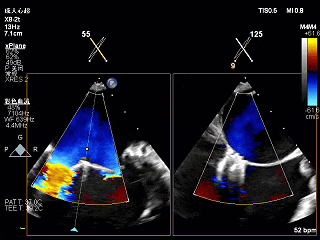

术前Bicom切面

术前X-Plane

3D-ZOOM 彩色多普勒显示反流主要来源于2区